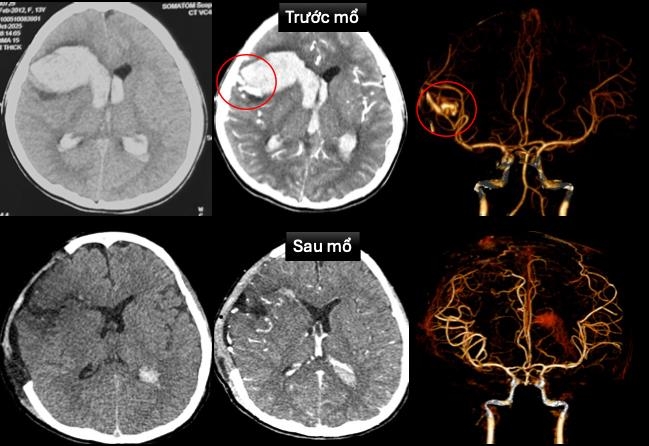

Tại Bệnh viện Nhi Đồng 1, bệnh nhi được tiến hành siêu âm tim và chụp cắt lớp vi tính dựng hình mạch máu não cấp cứu. Kết quả cho thấy bé bị dị dạng động tĩnh mạch vùng trán phải vỡ, gây xuất huyết não lan vào hệ thống não thất, đồng thời ghi nhận bệnh cơ tim xốp - một dạng bệnh cơ tim hiếm gặp.

Bệnh viện đã lập hội chẩn đa chuyên khoa gồm cấp cứu, tim mạch can thiệp, ngoại thần kinh và hồi sức ngoại. Bác sĩ tim mạch đặt máy tạo nhịp tạm thời để ổn định nhịp tim. Tiếp đó, ê-kíp ngoại thần kinh thực hiện mở sọ giải áp, vi phẫu cắt bỏ dị dạng mạch máu não và lấy máu tụ trong nhu mô não và não thất.

Sau phẫu thuật, bệnh nhi được hồi sức tích cực, thở máy, dùng thuốc vận mạch và thuốc chống phù não. Tình trạng cải thiện dần, hiện bé đã tỉnh táo, còn yếu nhẹ chân phải. Tim mạch ổn định, máy tạo nhịp đã được rút và ngưng thuốc vận mạch. Hình ảnh CT sau mổ không còn ghi nhận dị dạng mạch máu. Siêu âm tim cho thấy chức năng co bóp cơ tim cải thiện (EF 65%).